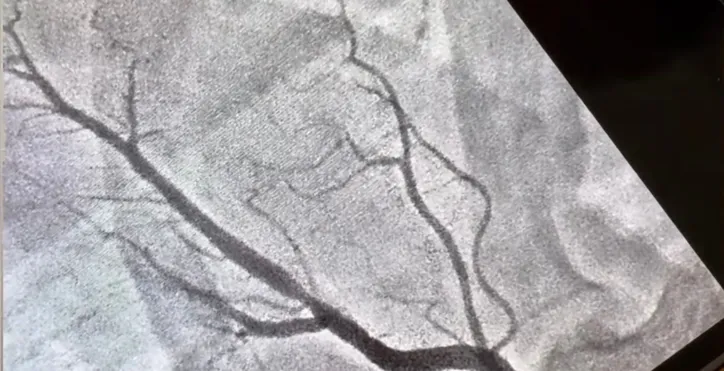

O stent é um pequeno tubo flexível de malha metálica, semelhante a uma mola, inserido em uma artéria obstruída para mantê-la aberta. De acordo com a médica Ludhmila Abrahão, que acompanhou o senador, o procedimento ajuda a evitar um infarto causado pela obstrução.

“O senador realizou exames de rotina e, durante a avaliação, foi detectada uma obstrução em uma das artérias do coração. Foi necessário colocar um stent, que funciona como uma espécie de mola, corrigindo o problema de forma preventiva e evitando o infarto”, explicou a médica.